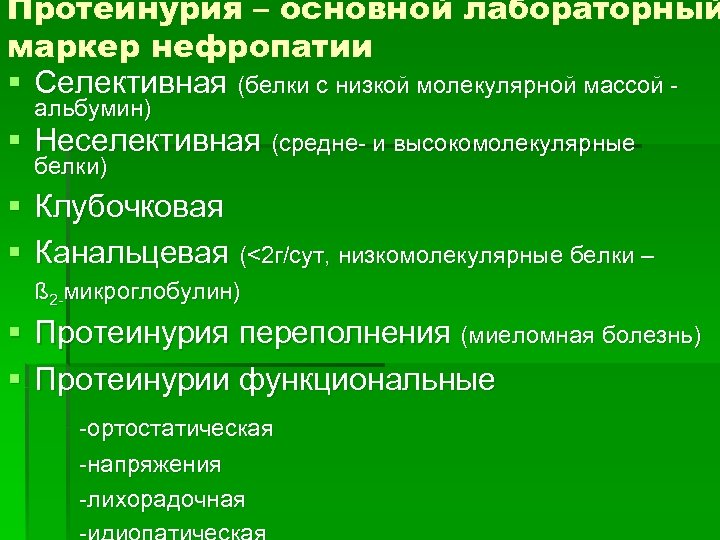

Протеинурия – основной лабораторный маркер нефропатии § Селективная (белки с низкой молекулярной массой альбумин) § Неселективная (средне- и высокомолекулярные белки) § Клубочковая § Канальцевая (<2 г/сут, низкомолекулярные белки – ß 2 -микроглобулин) § Протеинурия переполнения (миеломная болезнь) § Протеинурии функциональные -ортостатическая -напряжения -лихорадочная